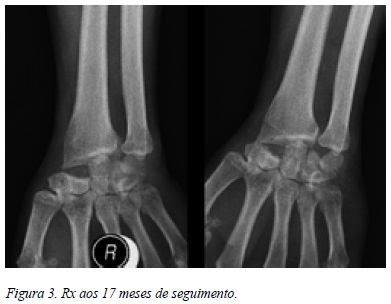

Com um seguimento de 13 meses, apresenta uma EVA de 2 pontos, amplitude de movimento combinado do punho de 60o, força de preensão de 28 kg e retomou as atividades de vida diária sem queixas. Radiologicamente não apresenta sinais de artrose radiocárpica e verificou-se integração do enxerto (Figura 3).